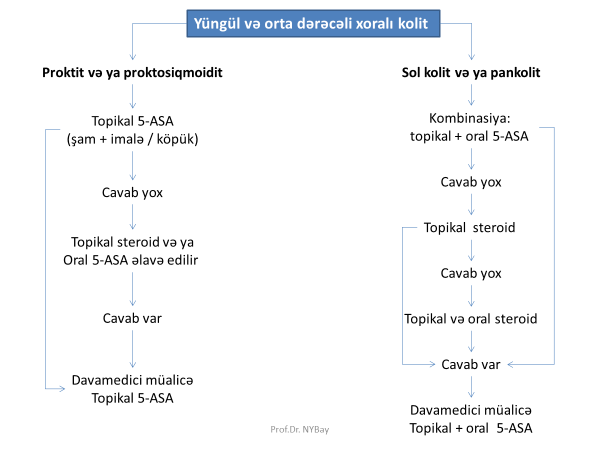

İBX müalicəsində hansı dərmanlar istifadə olunur?

- aminosalisilatlar: mesalamin, sulfasalazin

- immunosuppressorlar: azatioprin, steroid (prednizolon, hidrokortizon, budesonid)

- antibiotiklər: metronidazol, siprofloksin

- infliksimab

İBX uzun müddətli remissiya üçün müalicə seçimi hansıdır?

6-merkaptopurin, azatiopirin, mesalamin

İBX kəskinləşməsində ilk olaraq hansı dərmandan istifadə olunur?

Mesalamin və/və ya steroidlər

Steroid müalicəsinə cavab verməyən kəskinləşmələrdə nə edilir?

İmmunosupressor və ya infliksimab və ya cərrahi müalicə.

Xoralı kolitlərdə dərman verilməsinin özünəməxsus üsulu hansıdır?

İmalələr (steroid, 5-ASA)